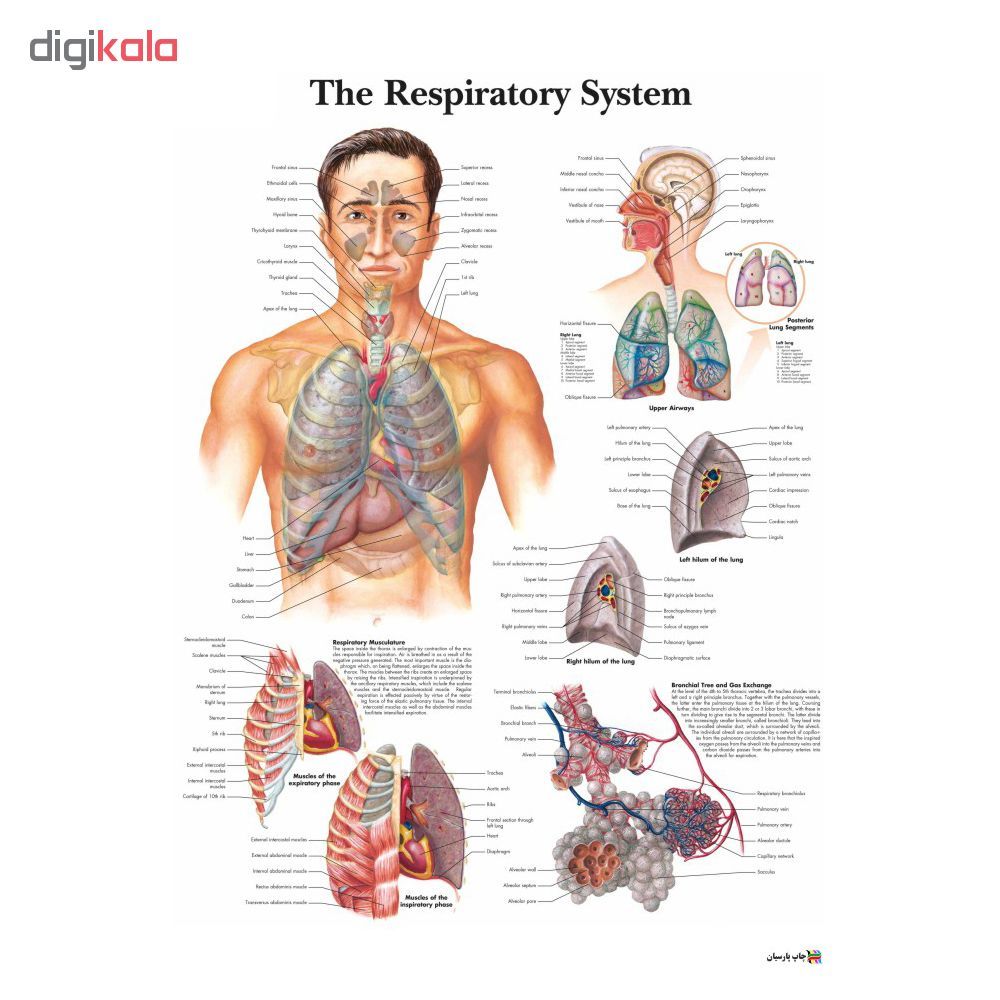

عکس اسکلت بدن انسان با کیفیت. عکس اسکلت عکس اسکلت برای پروفایل عکس اسکلت انسان عکس اسکلت خفن عکس اسکلت بدن انسان با کیفیت عکس اسکلت بدن انسان عکس اسکلت ترسناک عکس اسکلت فانتزی عکس اسکلت فانتزی دخترانه پرچم عکس اسکلت. عکس با کیفیت اسکلت داخلی انسان و درد و گرفتگی در ناحیه استخوان زانو ویژه استفاده در امور تبلیغاتی و تجاری طراحی کاتالوگ بروشور و تراکت با موضوع پزشکی فیزیوتراپی ارتوپد دکتر روماتیسم فیریوتراپ طب فیزیکی. عکس اسکلت بدن انسان زن و مرد آناتومی ساتین 16 سپتامبر 2017. اسکلت داربست بدن است تمام قسمت های بدن روی اسکلت قرارگرفته اند بدن انسان از ۲۰۶ قطعه استخوان تشکیل شده است این استخوان ها طوری با نظم کنار هم قرار گرفته اند که انسان را قادر می سازد حرکات دقیقی داشته باشد.

اسکلت جمجمه و گردن انسان ستون فقرات آناتومی اسکلت جمجمه و گردن انسان ستون فقرات آناتومی تصویر با کیفیت را از لینک زیر می توانید دانلود کنید. ۱ مطلب با کلمه ی کلیدی عکس اسکلت بدن انسان با کیفیت ثبت شده است گالری نسیم جدید ترین و با کیفیت ترین عکس های مناسبتی. عکس با کیفیت آناتومی اسکلت بدن انسان و درد و دیسک در قسمت مهره های ستون فقرات کمر ویژه استفاده در امور تبلیغاتی و تجاری طراحی کاتالوگ بروشور و تراکت با موضوع بیمارستان ها و کلینیک ها و درمانگاه ها و مطب ها پزشکان و.